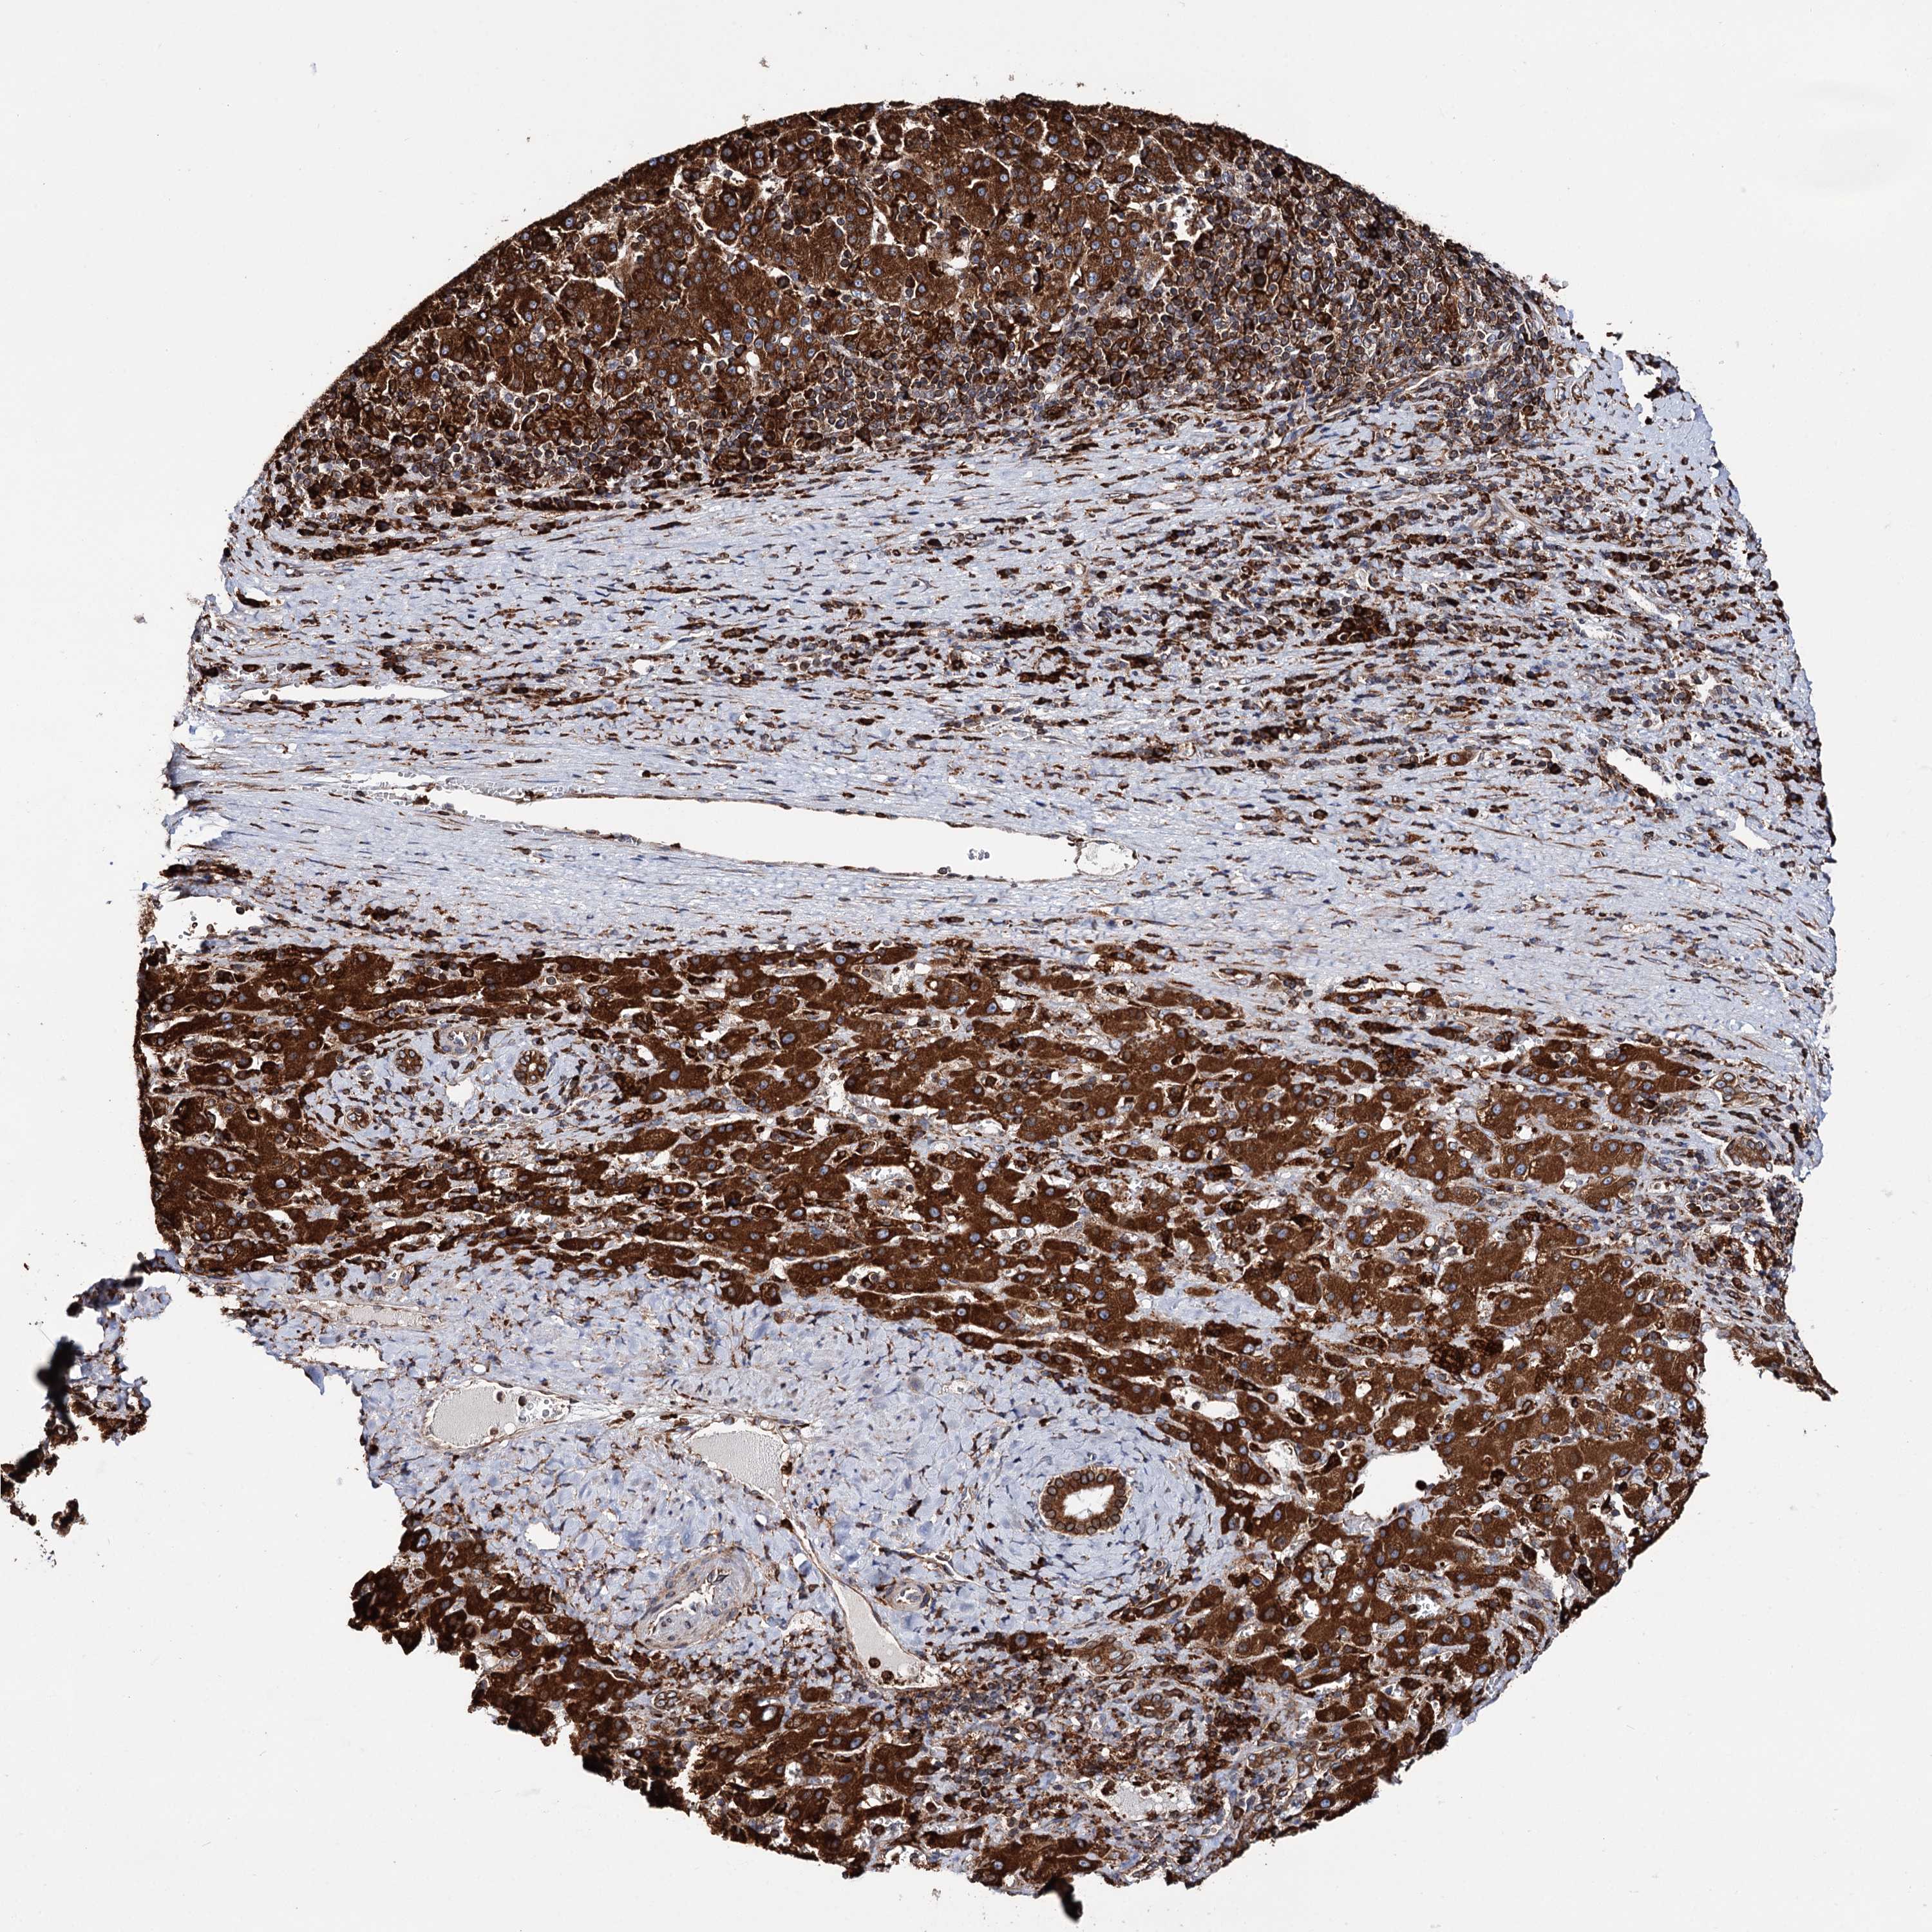

LIVER CANCER - Protein expressioni

A mouse-over function shows sample information and annotation data. Click on an image to view it in a full screen mode. Samples can be filtered based on level of antibody staining by selecting one or several of the following categories: high, medium, low and not detected. The assay and annotation is described here.

Note that samples used for immunohistochemistry by the Human Protein Atlas do not correspond to samples in the TCGA dataset.

Antibody stainingi

Antibody staining in the annotated cell types in the current human tissue is reported as not detected, low, medium, or high, based on conventional immunohistochemistry profiling in selected tissues. This score is based on the combination of the staining intensity and fraction of stained cells.

Each image is clickable and will lead to virtual microscopy that enables deeper exploration of all samples and also displays staining intensity scores, fraction scores and subcellular localization as well as patient and tissue information for each sample.

Antibody HPA039363

Antibody HPA039456

Staining

High

Medium

Low

Not detected

Intensity

Strong

Moderate

Weak

Negative

Quantity

>75%

75%-25%

<25%

None

Location

Nuclear

Cytoplasmic/membranous

Cytoplasmic/membranous,nuclear

Cholangiocarcinoma

Carcinoma, Hepatocellular, NOS